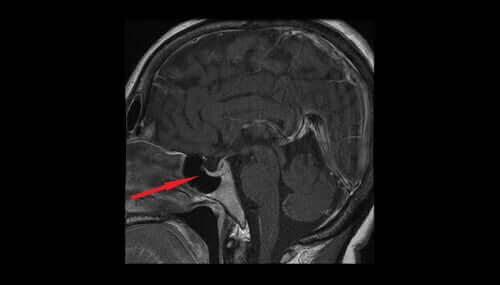

Лекарството Вазопресин, известен още като антидиуретичен хормон или ADH, идва от магноклетъчните ядра на хипоталамуса. От там преминава към неврохипофизата и накрая в кръвоносната система. Помага за регулиране на количеството вода в тялото като контролира количеството вода, което бъбреците изпускат. В тази статия ще разгледаме различните характеристики и ефекти от вазопресина.

Излишните нива на този антидиуретичен хормон могат да възникнат поради страничните ефекти от лекарства и заболявания на белите дробове, гръдната стена, хипоталамуса и хипофизната жлеза.

Ниските нива на антидиуретичния хормон ще накарат бъбреците да изпускат вода в излишък. Обемът на урината ще се увеличи и ще доведе до обезводняване и намаляване на кръвното налягане. Така че ниските нива на антидиуретичен хормон могат да подсказват за увреждания в хипоталамуса или хипофизната жлеза, или първична полидипсия.